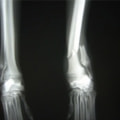

症例3:キルシュナーワイヤーのピンニングによる整復

ペルシャ猫 11ヶ月齢 雄

他院にて左大腿骨遠位の成長板骨折(salter-harrisⅠ型)が認められており、治療相談を目的として来院。当院にて、キルシュナーワイヤーを用いたピンニングにより骨折部位の整復を行いました。術後の経過は良好で、現在も経過観察中です。

術前レントゲン

術後レントゲン